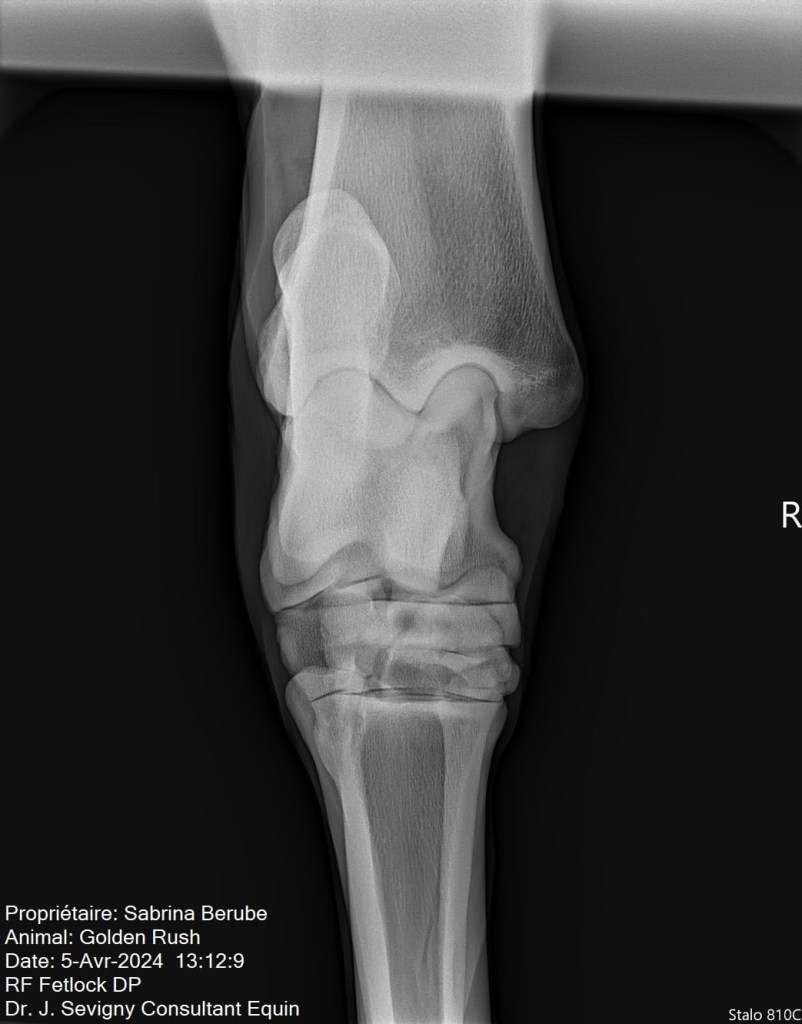

Par la suite, lors de la visite de ma vétérinaire, on a pris des radios de ses jarrets suite à son examen. Il n’a pas répondu tant que ça aux tests de flexion, mais tout de même il y a avait un petit quelque chose. Sur les radios, on a pu constater une présence d’arthrose modérée, ce qui venait expliquer le tout. Rien de surprenant vu son âge et sa discipline par contre, ce qui m’a rassurée un peu, mais je voulais traiter le problème. Je vous laisse les images pour vous donner une idée, je ne suis pas une experte en lecture de radio mais en gros, les espaces dans l’articulation sont sensés faire toute la longueur de l’articulation, mais dans le cas de mon cheval (surtout son jarret droit), l’arthrose est présente et fusionne les parties de l’articulation ensemble.